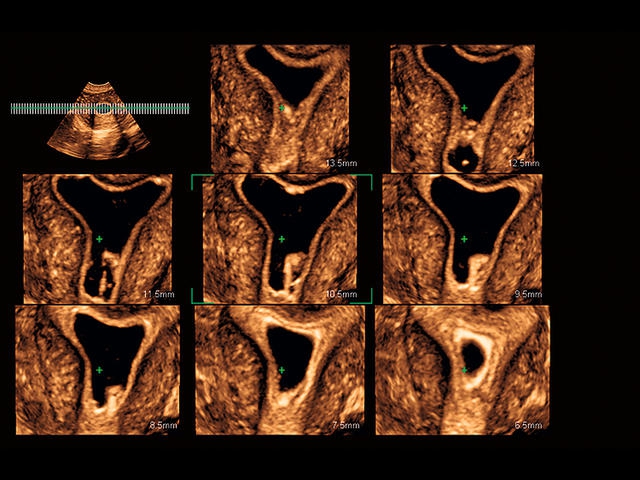

• Fly Thru. Виртуальная эндосонография обеспечивает построение трехмерной модели полостей, протоков и сосудов в рельном времени, облегчает организацию инвазивных процедур и динамических исследований. Посредством Fly Thru можно установить шунты и стенты, проводить точные оперативные вмешательства.